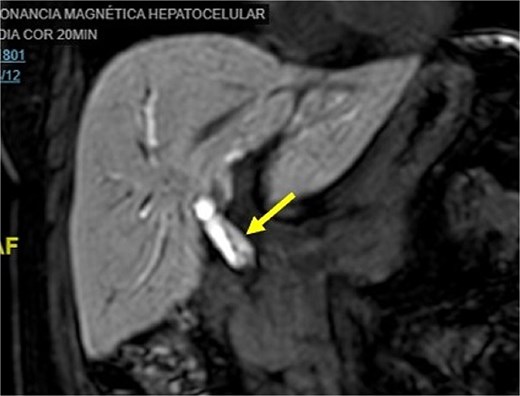

Initial imaging with ultrasound and computed tomography (CT) revealed intrahepatic bile duct dilatation without evidence of stones. Magnetic resonance cholangiopancreatography (Figs 1 and 2) showed a solid intraductal lesion extending from the left bile duct to the common bile duct, raising suspicion for IPNB versus MCN-L. SpyGlass endoscopy confirmed the presence of a solid intraductal tumor. Laboratory findings, including bilirubin, alpha-fetoprotein, and carcinoembryonic antigen, were within normal limits.

Magnetic resonance cholangiopancreatography image common bile duct intraductal tumor, coronal view.